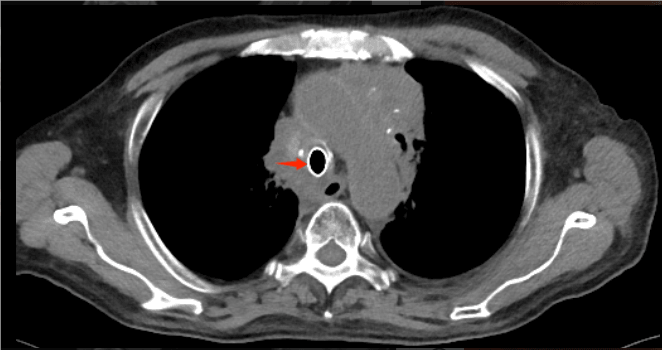

术后复查胸部CT见气道通畅